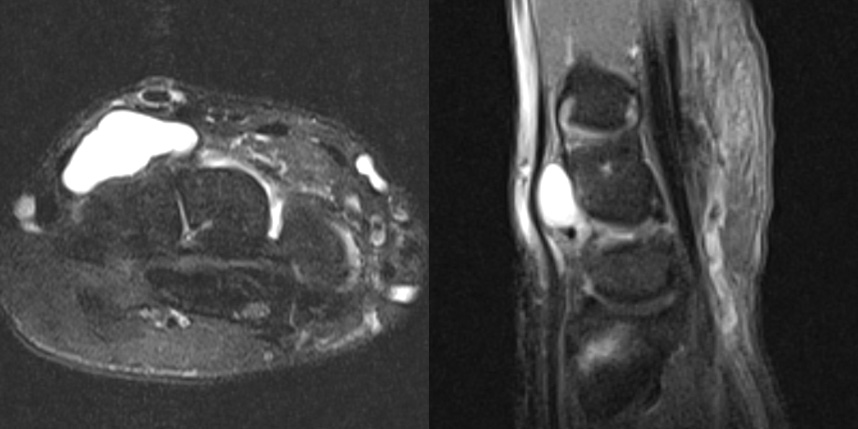

손등의 횡절개 방법은 가장 미용적이며, 상처에 의한 통증도 덜 남는 절개 방법으로 손등쪽 결절종에 경우 대부분 적용 가능합니다.

다음 사진들처럼 수술시 관절에 연결된 뿌리까지 찾아서 제거하여야 재발하지 않기 때문에 수술자의 기술이 특히 중요한 수술입니다.

상완신경총 마취를 주로 시행하며 1박 2일 정도의 입원이 권장됩니다.